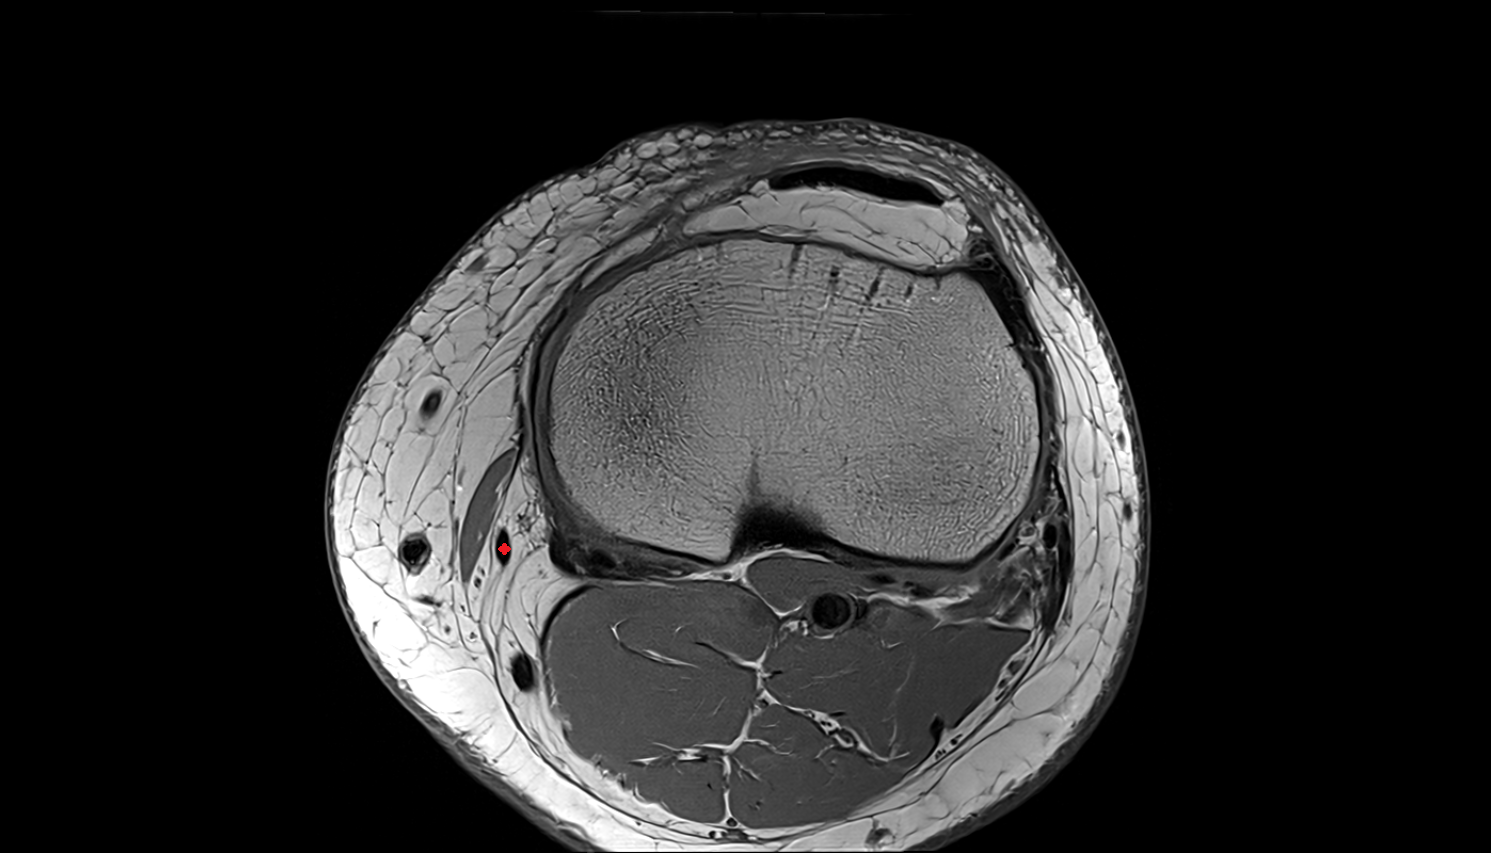

- Medial meniscus

- Lateral meniscus

- Patella

- Anterior cruciate ligament

- Posterior cruciate ligament